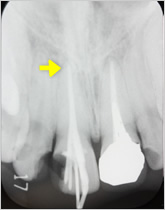

抜髄症例

主訴:3日前から何もしなくても前歯が痛む

- 虫歯が大きく神経まで達している為、虫歯を除去し抜髄

- ファイルを使って根の長さを測定・根管形成(根管-神経が入っていた管-を根管充填しやすい形に整えること)

- 根管充填剤が根尖(根の先端)まできっちりと充填